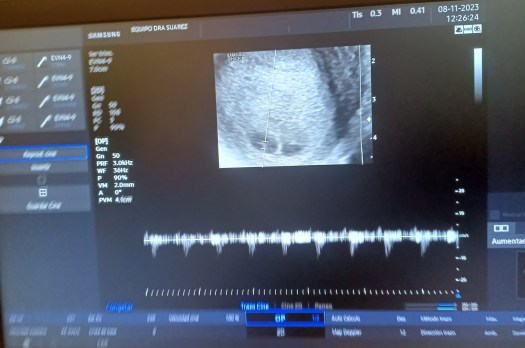

Sin embargo, en esa pequeña sala de reflexión había algo más. Vida, más Vida. Un hilo hilozoísta que atravesaba todos los corazones. Nos dimos la mano mientras llorábamos. Se hizo un silencio enorme y de repente, para nuestra sorpresa, se escuchó un pequeño latido acelerado. La emoción llenó la sala, la mayor expresión de alegría y esperanza se apoderó de nosotros. Felicidad, alegría, felicidad, alegría, y una gran esperanza contenida.

Allí, en esa pequeña cámara de reflexión, de Vida, se escucharon tres latidos. Uno pequeño, rápido y poderoso. Y dos grandes, a punto de explotar de la emoción. Tic, tac, tic, tac, tic, tac. Tres corazones en uno. Dos corazones latiendo en armonía en un mismo cuerpo y un tercero acompasando el ritmo desde el abrazo continuo. Magia, milagro, Vida, más Vida. Y esperanza, una gran esperanza, contenida, prudente aún, pero llena de gozo y de gracia. Tres latidos, así es el milagro sempiterno de la existencia. Así es el latido del Mundo.